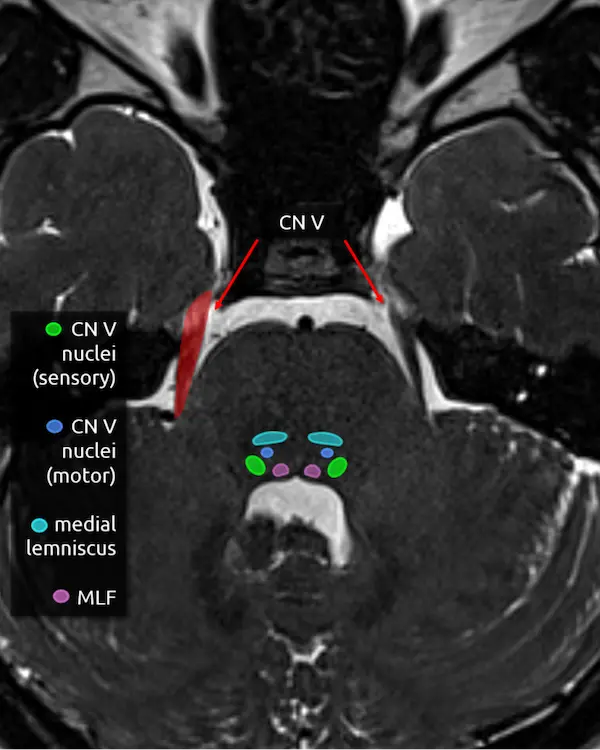

1. Corticospinal tracts

2. Transverse pontine fibers

3. Medial lemniscus

4. Medial longitudinal fasciculus (MLF)

5. Trigeminal nerve (CN V)

The trigeminal nerve is the largest cranial nerve. It exits the side of the pons approximately one slice above the internal auditory canals, then curves forward to traverse the CSF space in front of the pons called the prepontine cistern. It primarily provides sensory innervation to the face, mouth, anterior two thirds of the tongue, nasal sinuses, and dura mater. It has a smaller contribution to motor function of the muscles of mastication.

The trigeminal nerve is large enough to be at least partially visible on routine brain MRIs, though it is sometimes cut off or volume averaged along its course. Notice the image below looks slightly different. This is a heavily T2-weighted sequence with thin slices that is designed to maximize the contrast between CSF and CSF-surrounded structures, usually cranial nerves, blood vessels, or extra-axial lesions. These heavily T2-weighted sequences are useful for ruling out the most common identifiable cause of trigeminal neuralgia: compression by a blood vessel (i.e. neurovascular compression). The region of a cranial nerve most susceptible to symptomatic compression is called the transition zone (aka Obersteiner-Reidlich zone), which is a few millimeters-long gradient of transition from oligodendrocyte myelination (central) to Schwann cells (peripheral). These transition zones are close to where the nerve emerges from the brainstem, called the root entry zone. For the trigeminal nerve, it is 3-4 mm away.

The trigeminal nerve has four nuclei, and two are located around this level.

6. Main sensory nucleus of the trigeminal nerve (CN V)

The main sensory nucleus of the trigeminal nerve is located in the posterolateral pons near the margin of the fourth ventricle approximately one slice above the internal auditory canals.

Lesions in this area will cause ipsilateral sensory loss of the face. A small white matter tract that carries pain and temperature sensation to the body, called the spinothalamic tract (see level 5), is in this region and may be damaged at the same time, resulting in an ipsilateral facial sensory deficit and contralateral body sensory deficit.

7. Motor nucleus of the trigeminal nerve (CN V)

The motor nucleus of the trigeminal nerve is small and located anterior and medial to the main sensory nucleus. As mentioned above, it provides motor innervation to the muscles of mastication primarily, but also to some smaller muscles in the ear and face, for example the tensor tympani muscle and tensor veli palatini.

Damage here may be detectable as weakness and deviation of the mandible or atrophy of the ipsilateral muscles of mastication.